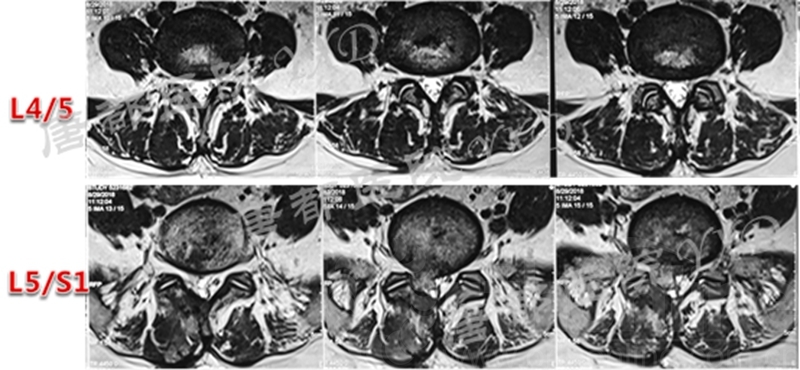

影像学检查:

诊断:腰椎间盘突出症术后复发

手术方案:显微镜辅助MI-TLIF腰椎翻修术

术中视频:http://api.orthonline.com.cn/attach/Case2.mp4(术中发现因前三次侧路及后路内镜手术的操作,术区大量瘢痕组织增生、与神经粘连严重;此外,摘除头侧游离髓核时连接有软骨终板脱落;在显微镜操作下,安全地将神经进行充分松解,压迫神经的游离髓核及软骨终板彻底清除。无手术并发症)